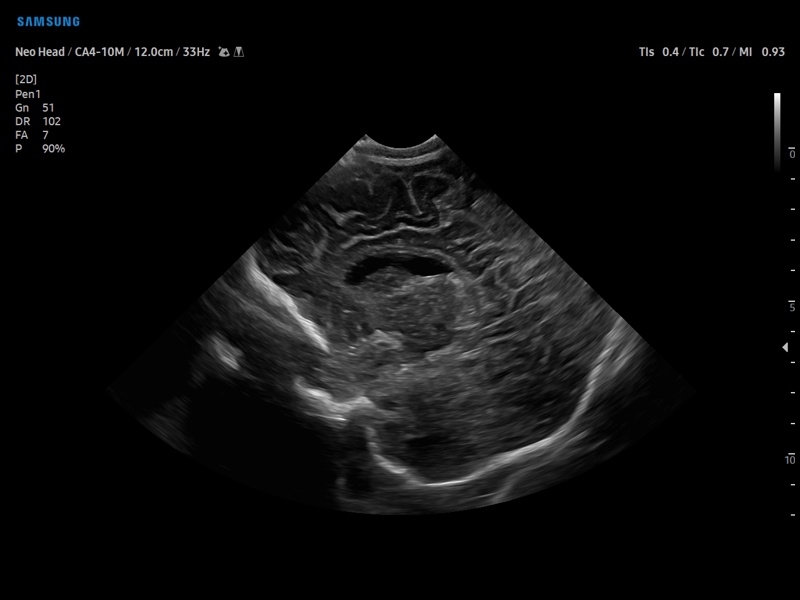

• Модуль5D CNS– программа автоматического построения основных срезов головного мозга плода в режиме объемного сканирования.

• MSV(Multi-Slice View илимультислайсинг) - возможность одновременного просмотра на экране множественных срезов, полученных при трехмерном сканировании.

• VolumeCT - трехмерная реконструкция изображений в виде куба (Cube Sectional View) или трех пересекающихся плоскостей (Cross View).